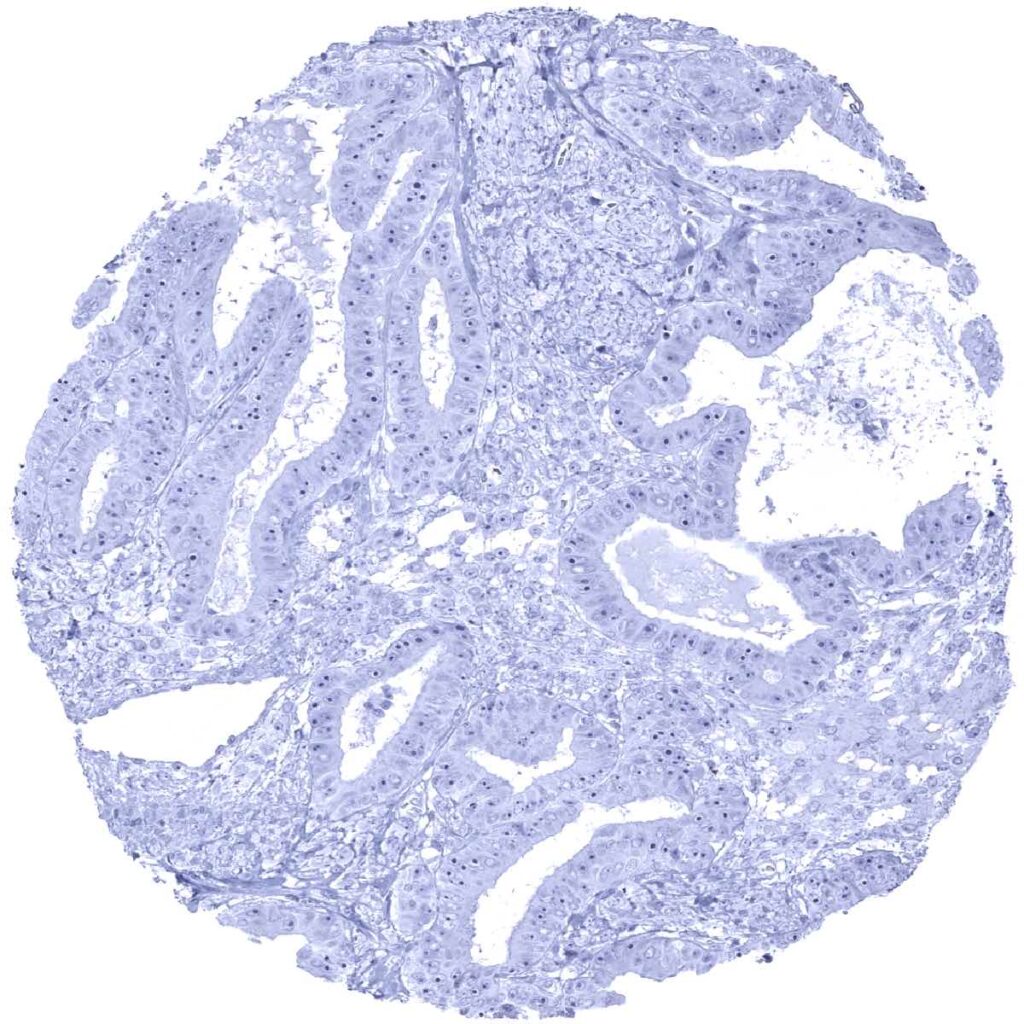

Colon- p63 negative colorectal adenocarcinoma